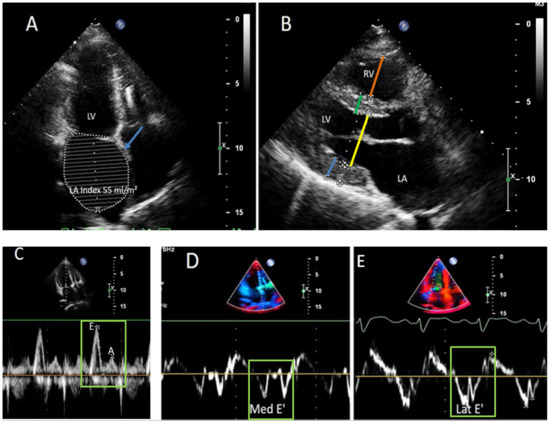

Clinical, Genetic, and Histological Characterization of Patients with Rare Neuromuscular and Mitochondrial Diseases Presenting with Different Cardiomyopathy Phenotypes

Cardiomyopathies are mostly determined by genetic mutations affecting either cardiac muscle cell structure or function. Nevertheless, cardiomyopathies may also be part of complex clinical phenotypes in the spectrum of neuromuscular (NMD) or mitochondrial diseases (MD). The aim of this study is to describe [...] Read more.

Cardiomyopathies are mostly determined by genetic mutations affecting either cardiac muscle cell structure or function. Nevertheless, cardiomyopathies may also be part of complex clinical phenotypes in the spectrum of neuromuscular (NMD) or mitochondrial diseases (MD). The aim of this study is to describe the clinical, molecular, and histological characteristics of a consecutive cohort of patients with cardiomyopathy associated with NMDs or MDs referred to a tertiary cardiomyopathy clinic. Consecutive patients with a definitive diagnosis of NMDs and MDs presenting with a cardiomyopathy phenotype were described. Seven patients were identified: two patients with ACAD9 deficiency (Patient 1 carried the c.1240C>T (p.Arg414Cys) homozygous variant in ACAD9; Patient 2 carried the c.1240C>T (p.Arg414Cys) and the c.1646G>A (p.Ar549Gln) variants in ACAD9); two patients with MYH7-related myopathy (Patient 3 carried the c.1325G>A (p.Arg442His) variant in MYH7; Patient 4 carried the c.1357C>T (p.Arg453Cys) variant in MYH7); one patient with desminopathy (Patient 5 carried the c.46C>T (p.Arg16Cys) variant in DES); two patients with mitochondrial myopathy (Patient 6 carried the m.3243A>G variant in MT-TL1; Patient 7 carried the c.253G>A (p.Gly85Arg) and the c.1055C>T (p.Thr352Met) variants in MTO1). All patients underwent a comprehensive cardiovascular and neuromuscular evaluation, including muscle biopsy and genetic testing. This study described the clinical phenotype of rare NMDs and MDs presenting as cardiomyopathies. A multidisciplinary evaluation, combined with genetic testing, plays a main role in the diagnosis of these rare diseases, and provides information about clinical expectations, and guides management. Full article